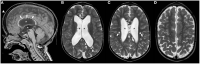

Macrocephaly affects up to 5% of the pediatric population and is defined as an abnormally large head with an occipitofrontal circumference (OFC) >2 standard deviations (SD) above the mean for a given age and sex. Taking into account that about 2-3% of the healthy population has an OFC between 2 and 3 SD, macrocephaly is considered as "clinically relevant" when OFC is above 3 SD. This implies the urgent need for a diagnostic workflow to use in the clinical setting to dissect the several causes of increased OFC, from the benign form of familial macrocephaly and the Benign enlargement of subarachnoid spaces (BESS) to many pathological conditions, including genetic disorders. Moreover, macrocephaly should be differentiated by megalencephaly (MEG), which refers exclusively to brain overgrowth, exceeding twice the SD (3SD-"clinically relevant" megalencephaly). While macrocephaly can be isolated and benign or may be the first indication of an underlying congenital, genetic, or acquired disorder, megalencephaly is most likely due to a genetic cause. Apart from the head size evaluation, a detailed family and personal history, neuroimaging, and a careful clinical evaluation are crucial to reach the correct diagnosis. In this review, we seek to underline the clinical aspects of macrocephaly and megalencephaly, emphasizing the main differential diagnosis with a major focus on common genetic disorders. We thus provide a clinico-radiological algorithm to guide pediatricians in the assessment of children with macrocephaly.